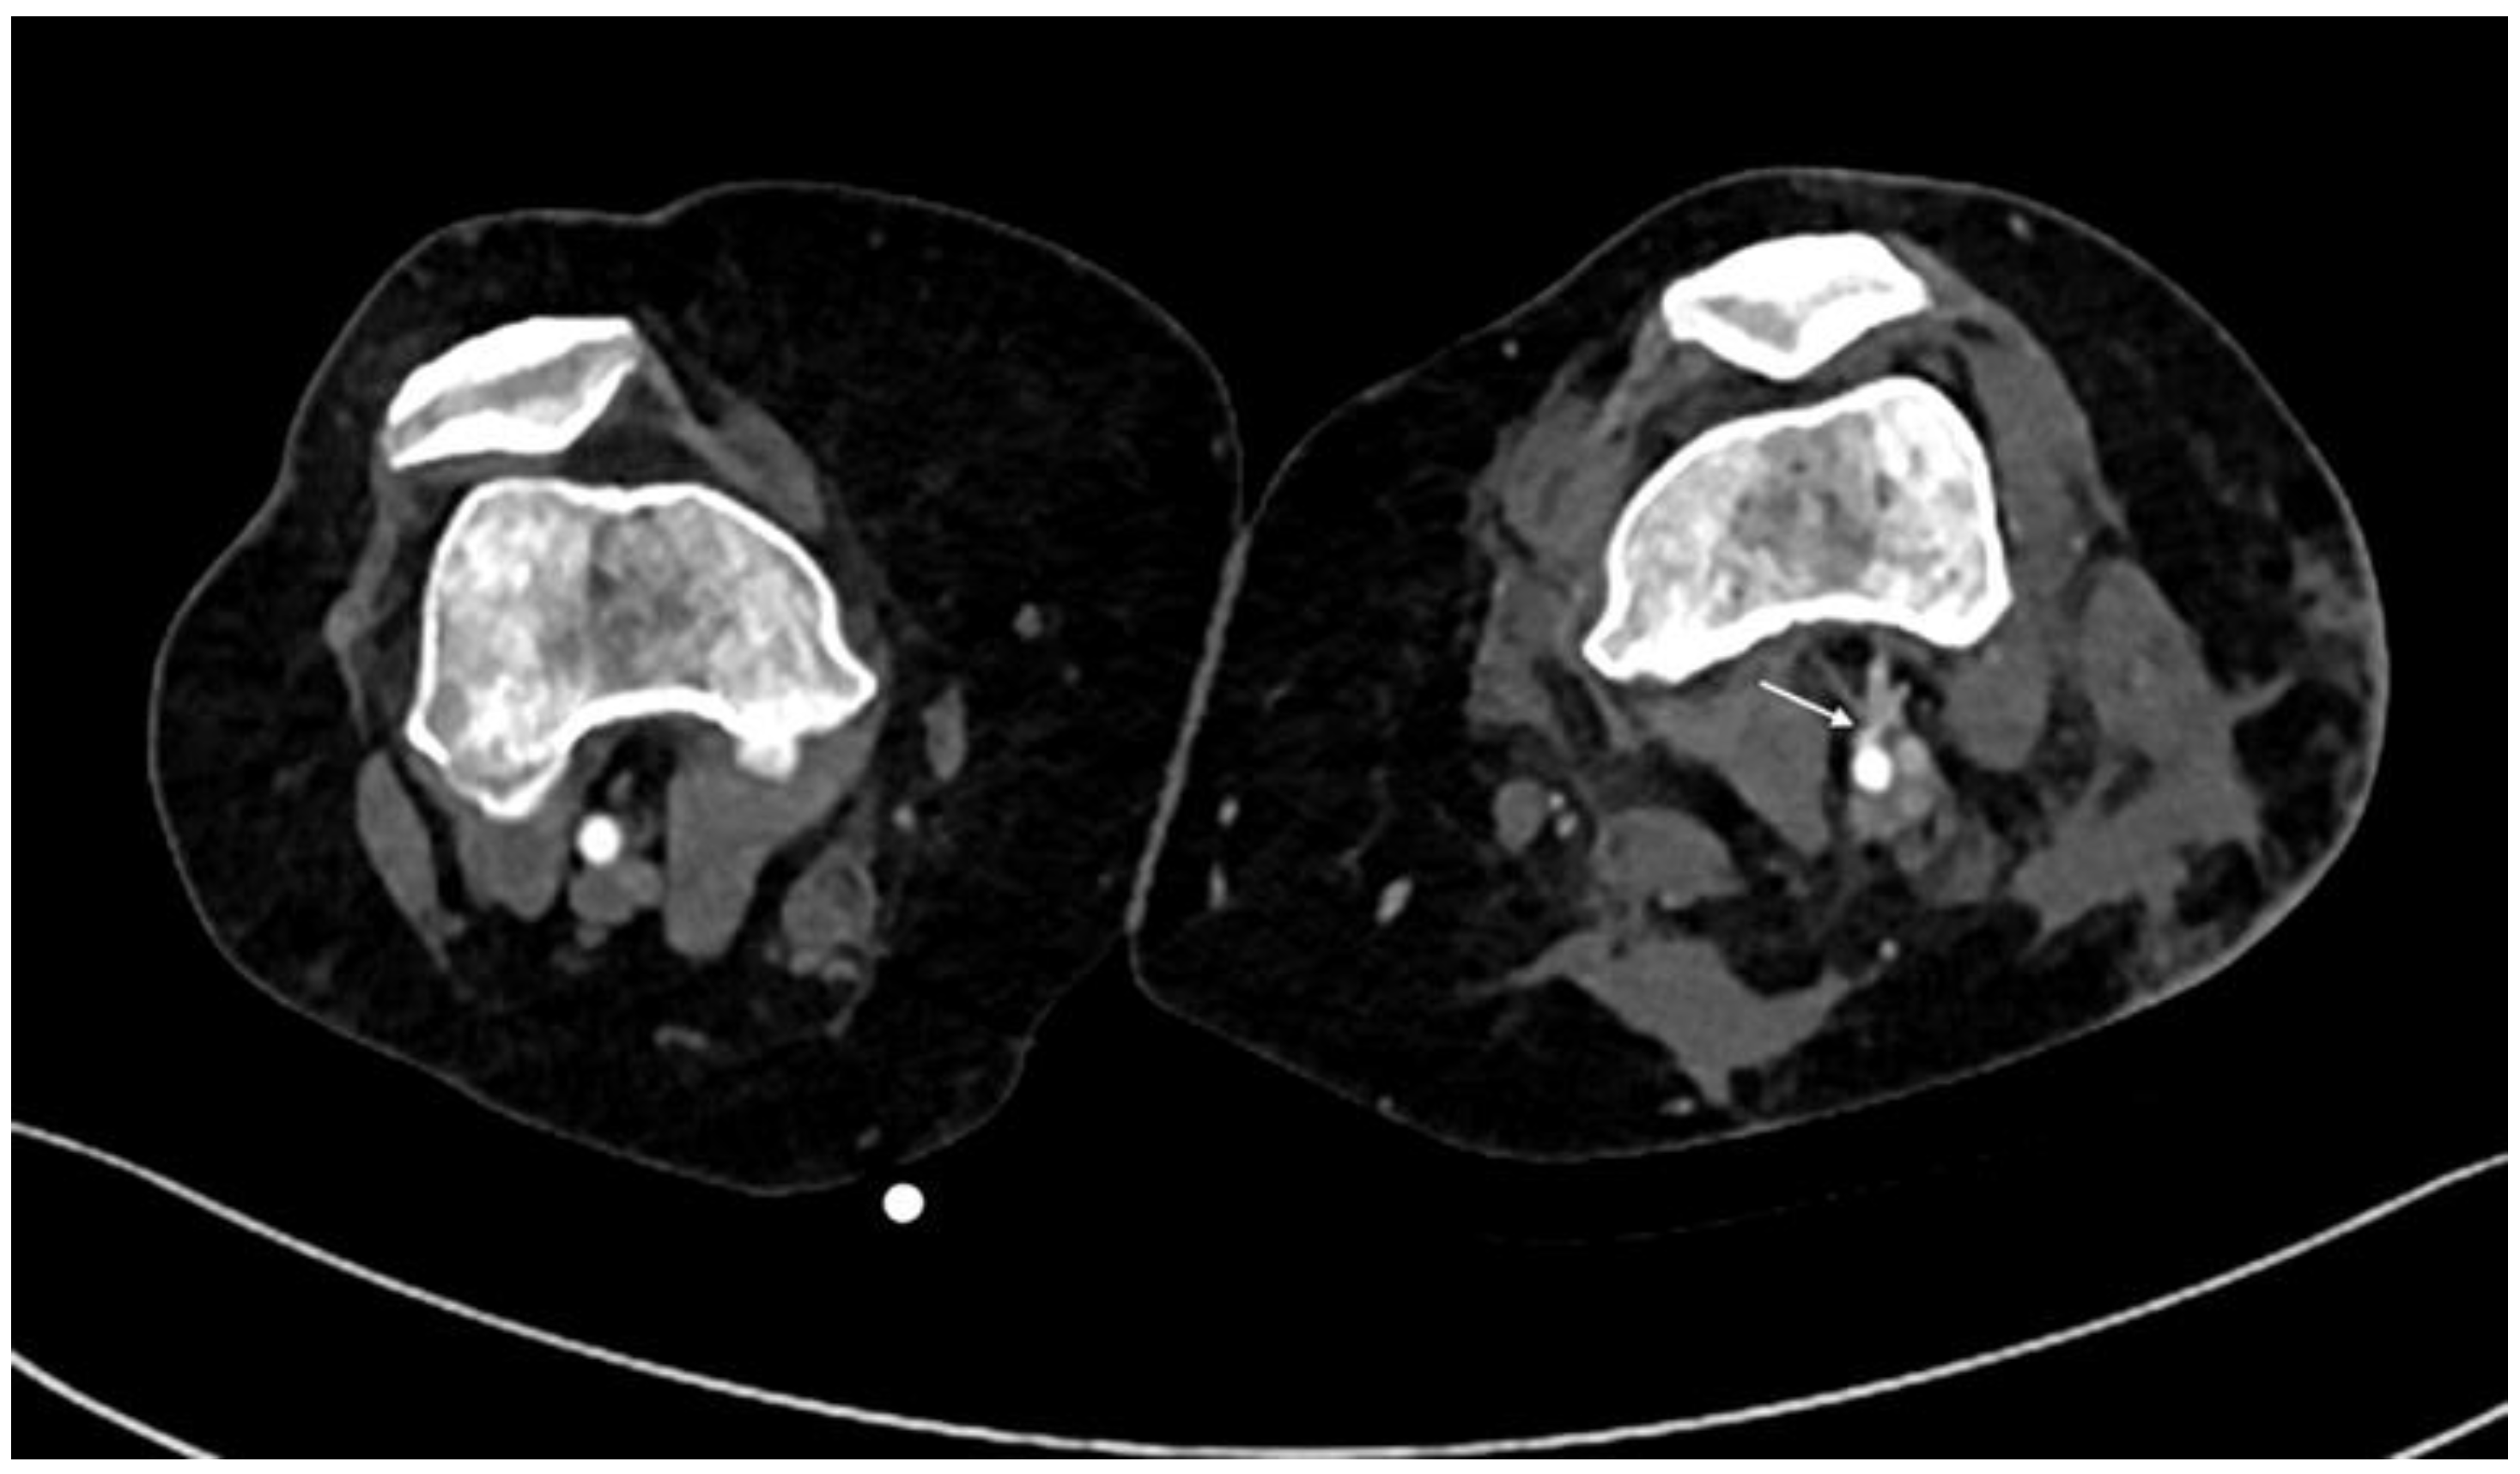

3.2. CTA Imaging Findings

- Gakhal, M.S.; Sartip, K.A. CT angiography signs of lower extremity vascular trauma. AJR Am. J. Roentgenol. 2009, 193, W49–W57. [Google Scholar] [CrossRef] [PubMed]

- Miller-Thomas, M.M.; West, O.C.; Cohen, A.M. Diagnosing traumatic arterial injury in the extremities with CT angiography: Pearls and pitfalls. Radiographics 2005, 25 (Suppl. S1), S133–S142. [Google Scholar] [CrossRef] [PubMed]

- Madhuripan, N.; Mehta, P.; Smolinski, S.E.; Njuguna, N. Computed Tomography Angiography of the Extremities in Emergencies. Semin. Ultrasound CT MR 2017, 38, 357–369. [Google Scholar] [CrossRef] [PubMed]